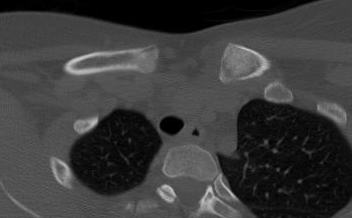

CT scan

Left posterior SCJ dislocation with pre- and post angiogram

Severe left posterior SCJ dislocation with subclavian vein compression